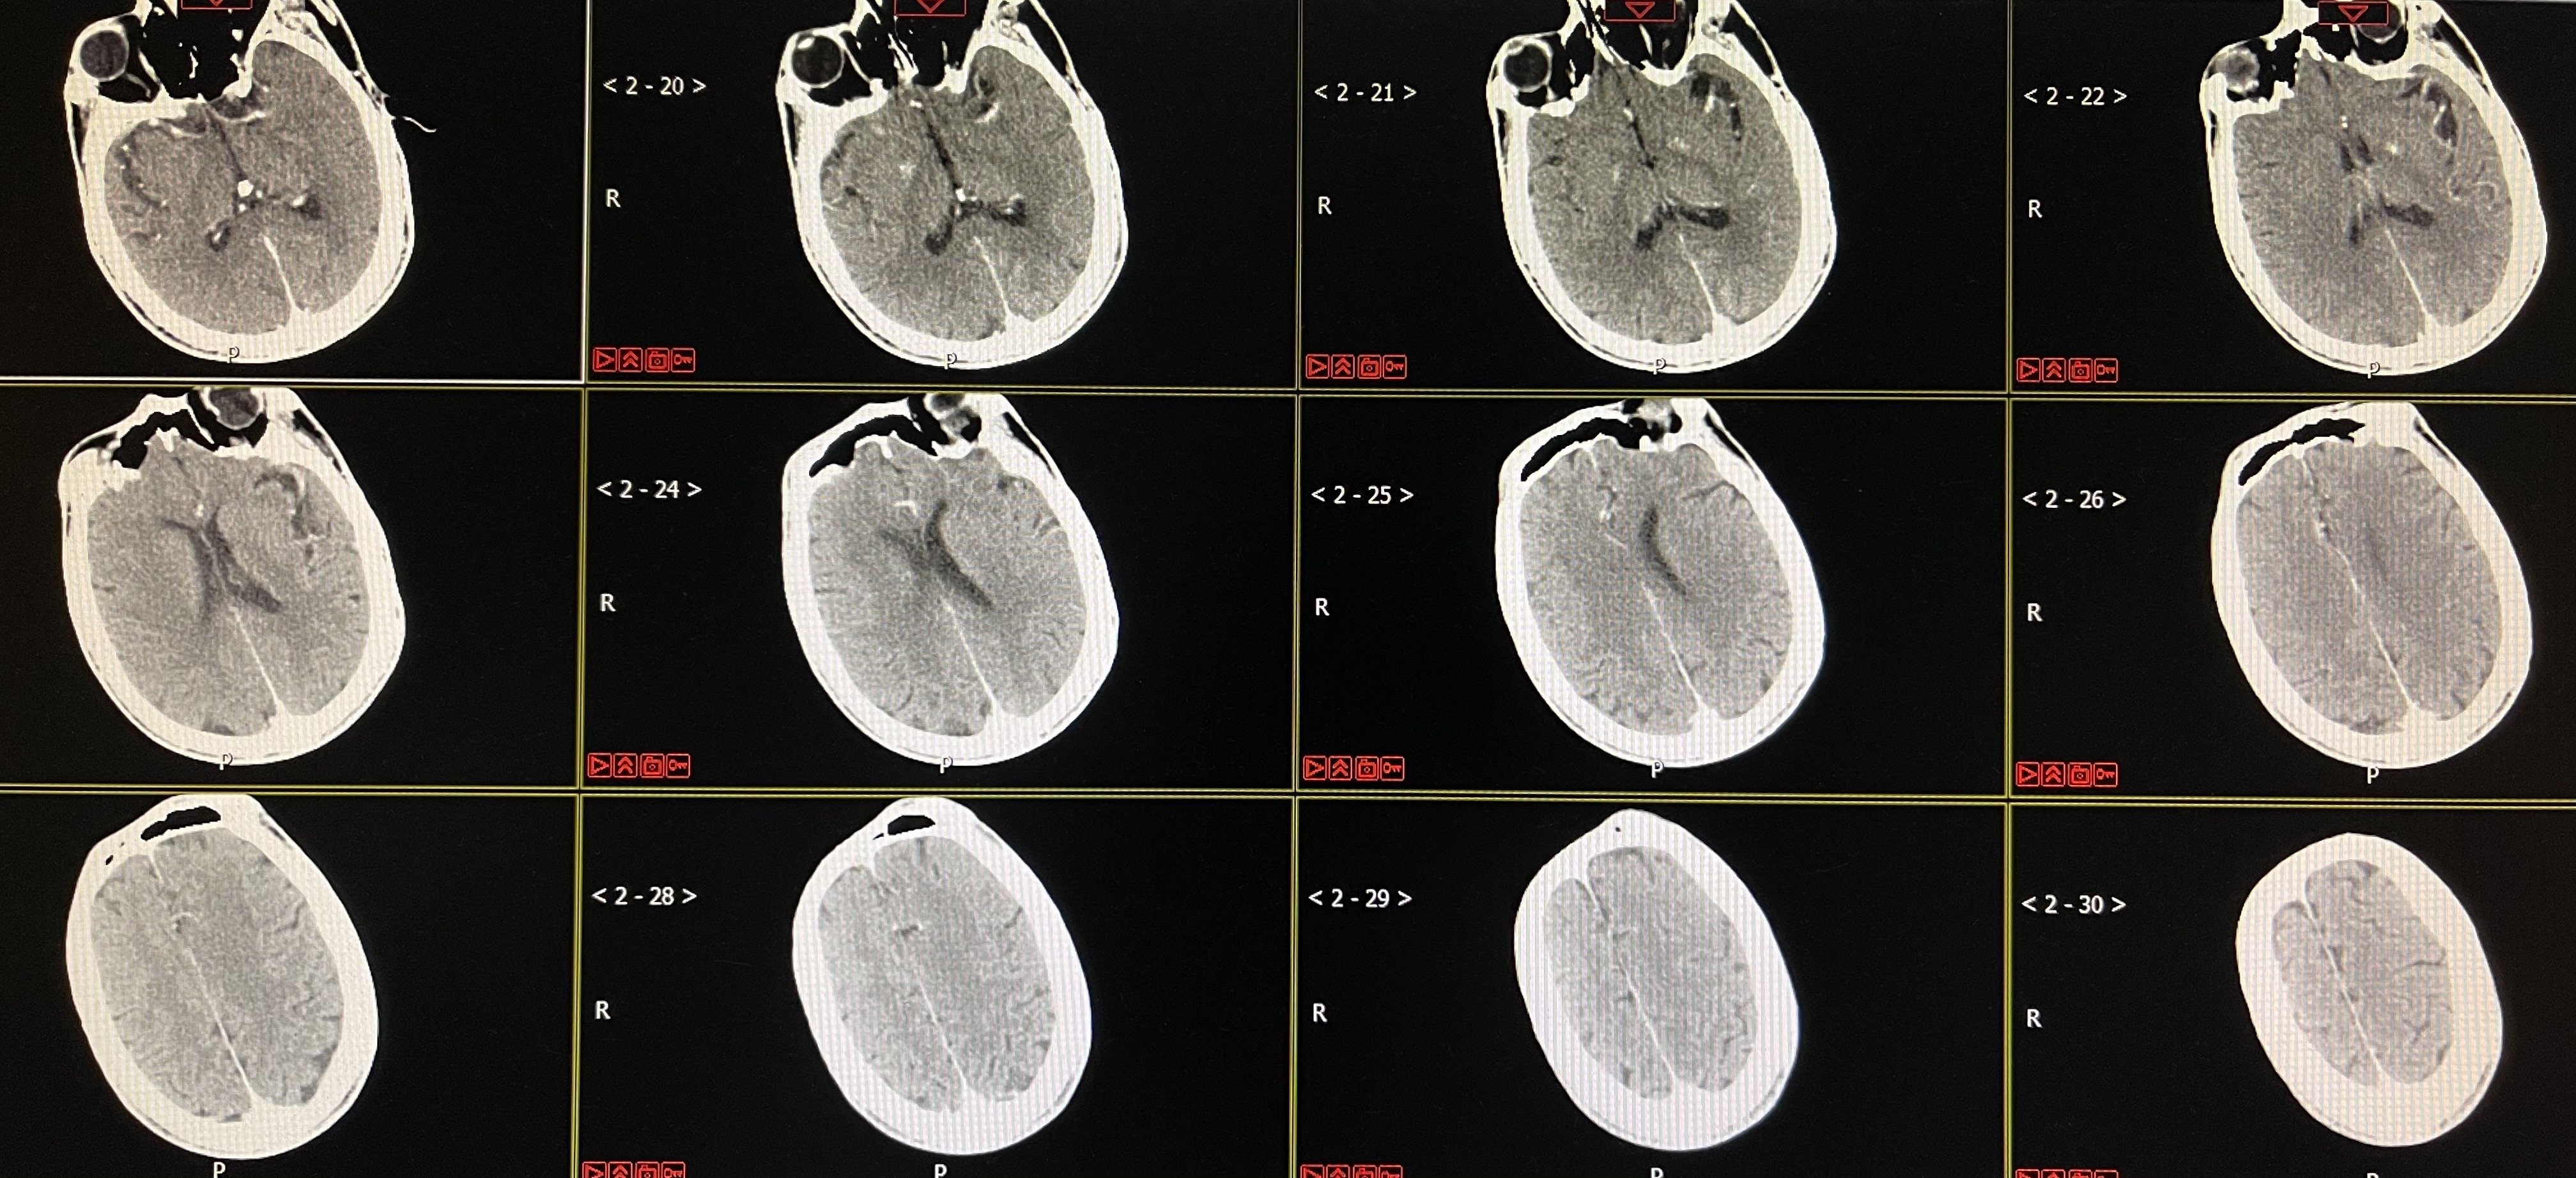

术后即刻CT